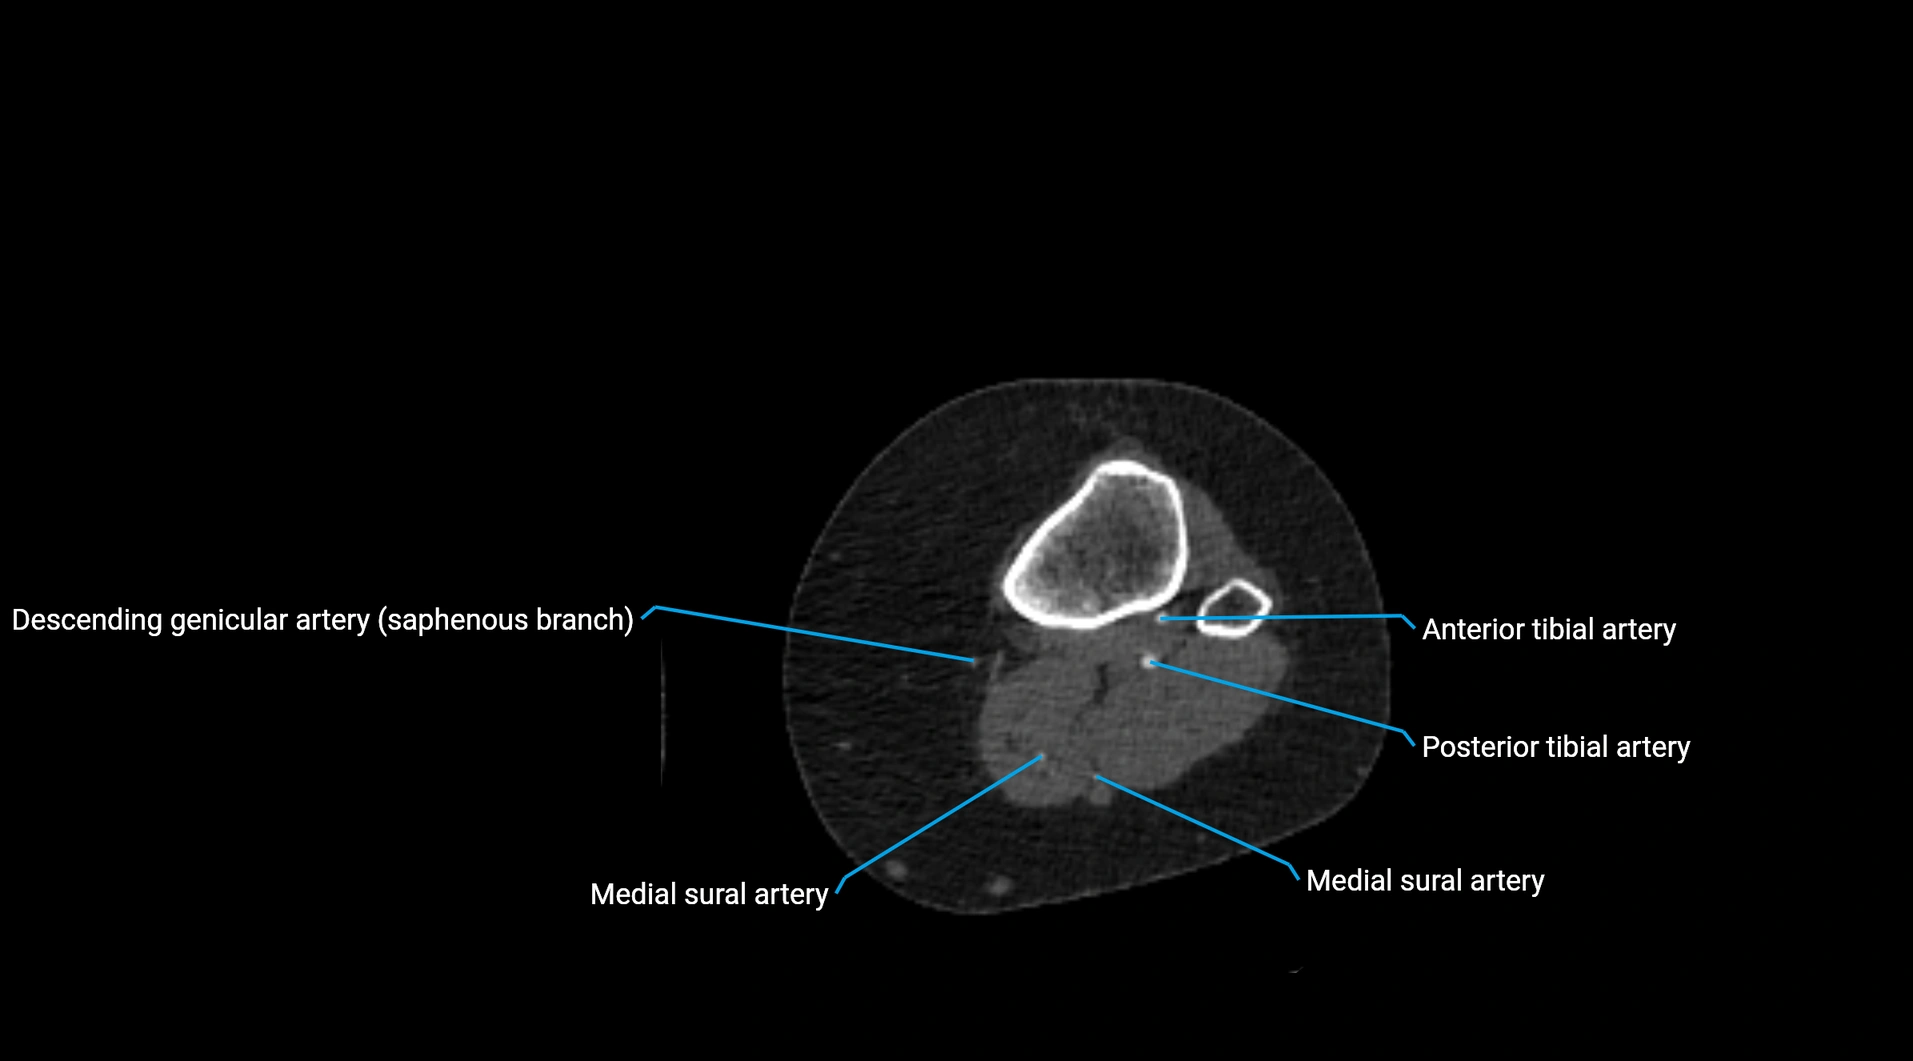

Contrast-enhanced CT (CTA):

• Gold standard for abdominal aortic imaging

• Provides excellent detail of lumen, wall, aneurysm, thrombus, and branch vessels

• Multiplanar and 3D reconstructions help in aneurysm measurement, stent graft planning, and dissection evaluation

• Detects acute rupture, traumatic injury, or occlusion with high sensitivity